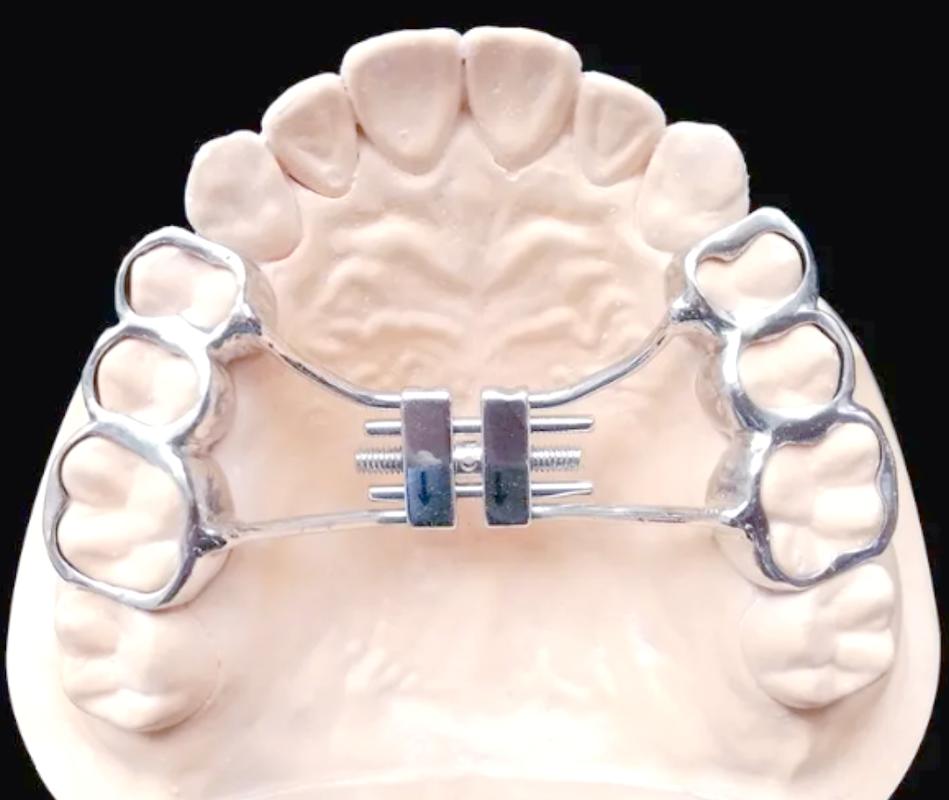

活动矫治器

- 特点: 由塑料基托和金属丝弹簧、螺钉等附件组成,用于简单的牙齿移动(如个别牙扭转、间隙关闭)或作为功能性矫治器的辅助。

活动矫治器图片,removable orthodontic appliance,简单活动矫治器 - 优点: 患者可自行摘戴,便于清洁,价格相对便宜。

- 缺点: 控制力较弱,适用范围有限,依赖患者配合度。